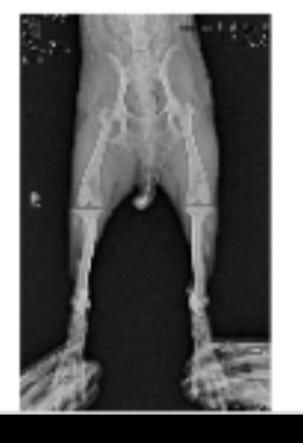

- 반려동물 건강반려동물보통은호감이넘치는차장강아지 슬개골 수술 4달 반 후 절뚝거림2월 5일에 양쪽 다리 슬개골 4기 판정 받고 수술 후 얼마 전까지 문제 없이 잘 걷다가 며칠 전부터 왼쪽 다리를 걸을 때 절뚝 거린다해야 하나 부자연스러운 느낌이 있어요 그리고 앉을 때도 왼쪽 발을 띄운 상태로 털석 앉아버리구요 ㅠ며칠 동안 다칠 일이 있었다거나 그런 게 아예 없었고 평소랑 너무 똑같았는데 지금도 크게 아프진 않은지 집안에서 짧은 거리 살짝씩 뛰기도 하구요 재발은 아니겠죠? 왜 그러는 걸까요 ㅠ검사 당시에 슬개골 이외에 고관절은 너무 건강하다 했었고 다른 곳도 이상 없다고 하셨어요1명의 전문가가 답변했어요